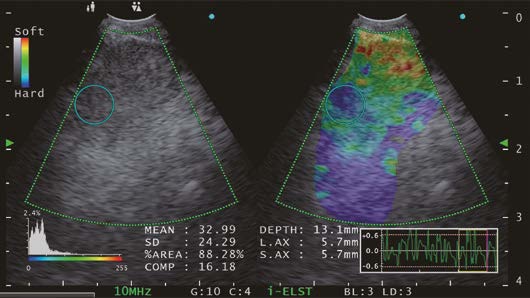

ELST Mode (i-ELST)

Case) 70 years old male patient presented himself 6 years and 10 months after thoracoscopic resection surgery for lung cancer in the right lower lobe.

A nodule in the left lung and an enlarged mediastinal lymph node was identified at a different hospital. The patient was subsequently referred to our hospital for further evaluation and management.

In this case, blood flow was observed in the upper right of the lymph node where the needle would pass through, so it was necessary to avoid this area when puncturing the lymph node.

The selection of the puncture site was determined by using the ELST mode. The EU-ME3 with its newly equipped “i-ELST function”, enables to display stable ELST images even with minute vibrations. The ELST images were green at the center of the lymph node and predominantly blue at the margins of the lymph node.

It has been reported that a combination of ELST and B-mode images is useful for identifying the most suspected site of the lymph node when performing EBUS-TBNA.*

As described above, we were able to collect viable tumor cells and the core by adjusting the puncture site and puncturing the node referring to the ELST mode images.

Small cell carcinoma was suspected by rapid on-site cytologic evaluation during EBUS-TBNA and immediately confirmed by a pathologist. We determined pleural dissemination and diagnosed stage IV small cell carcinoma. Chemotherapy with CBDCA + VP-16 + Durvalumab was started.

Moreover, the utilization of Elastography mode during procedures or playback measurements with recorded Elastography mode images from the EU-ME3’s internal memory allows for the collection of Strain Ratio* and Strain Histogram**. As previously reported2),3), Elastography offers essential parameter data to assess tissue stiffness (elasticity) in a specific region of interest (ROI). In my view, the integration of i- Elastography with convex-probe endobronchial ultrasound could prove to be a valuable tool for predicting and precisely locating metastatic lymph nodes during EBUS-TBNA in the future.

*The Strain ratio is calculated as the ratio between the strain in the reference tissue of the region of interest and the strain within the target lesion of the ROI. The higher the strain ratio, the stiffer the lesion.

**In strain histogram analysis, lesion stiffness is calculated as mean pixel color values of a single ROI within the target lesion. Values range from 0 to 255 (from blue over green to red). Increasing lesion stiffness causes a decrease in mean histogram values.